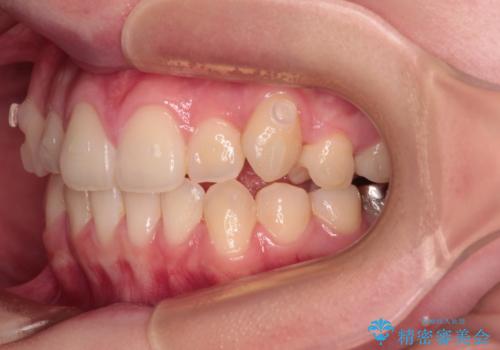

補助装置を使用したことで、口元が突出することもなく、スムーズに仕上げることができました。